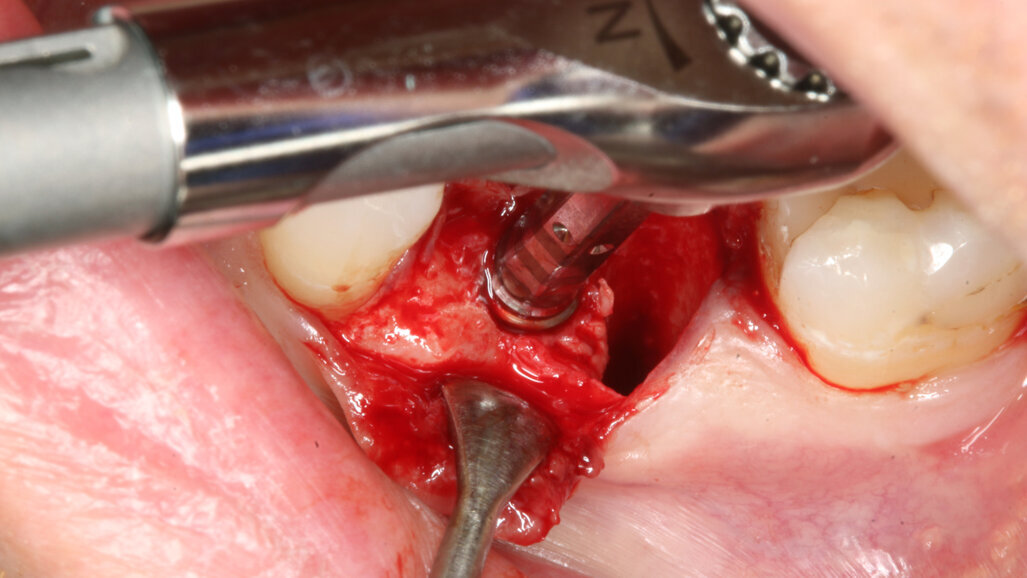

The implant site was prepared following the recommended drilling protocol for the planned PrimeTaper EV 4.2 mm diameter implant (drills #1, 3 and 4; Fig. 2). After cortical preparation with drill #5, the implant was placed. The preparation was finalised with a tap, owing to dense trabecular bone (Fig. 3). The implant was inserted to a torque of 42 Ncm (Fig. 4).